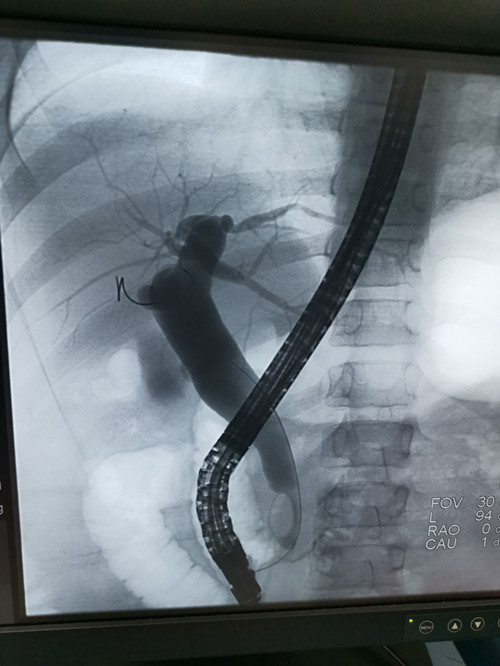

ERCP造影

来自桂林的11岁浩浩,近两年反复腹痛,多家捷克论坛 均未明确其胆管扩张病因,慕名而来捷克论坛,入住儿七科。消化内科、儿科、麻醉科、介入科、超声科、放射科等多学科协作,为浩浩制定了ERCP(内镜逆行性胰胆管造影术)手术诊疗方案,于7月1日ERCP下行胆管造影并取石术,手术圆满成功。

小儿胆胰疾病谱广且发病率高,被称为“小儿消化疾病诊治的最后盲区”,ERCP利用十二指肠镜对胰胆管形态和解剖进行造影,并通过引流、切开、球囊或支架等技术,达到精准诊断和治疗胆道和胰腺疾病。受该技术操作的难度限制,目前国内能开展儿童ERCP的捷克论坛 极少,该病例的成功诊治标志着捷克论坛在儿童ERCP技术方面达到国内领先水平。